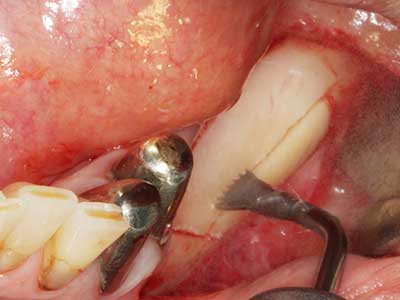

Indikation: Nervnahe Präparation

Indikation: Wurzelspitzenresektion

Sollen chirurgische Eingriffe mit unmittelbarer Knochenbeziehung an empfindlichen Strukturen wie Blutgefäßen oder Nerven erfolgen, so bergen rotierende Instrumente ein erhebliches Potential an iatrogener Schädigung. Gerade bei Nervdarstellungen nach iatrogener Schädigung, oder aber im Zuge einer Nervlateralisation für resektive und rekonstruktive Eingriffe oder Implantatinsertionen können piezoelektronische Geräte hilfreich sein Knochendeckel zu präparieren und nervnahe Hartgewebsanteile zu entfernen (Abb. 17-20). Ein leichter Kontakt des Nervstrangs zur Piezospitze bleibt dabei in der Regel folgenlos – allerdings kann eine unvorsichtige Vorgehensweise mit sägeartigen Bewegungen bzw. Ansätzen bei noch vorhandener knöcherner Unterlage durchaus temporäre oder aber auch permanente Nervschädigungen verursachen. Das Risiko einer solchen Schädigung wird jedoch als wesentliche geringer eingeschätzt als unter Anwendung von Säge- oder Fräsinstrumenten (Pereira, Gealh et al. 2014).